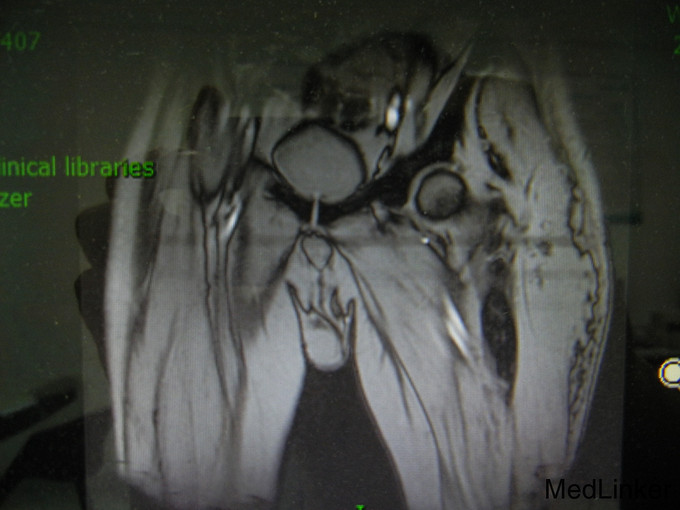

男,51岁 因“发现左臀部包块疼痛进行性加重20余日”入院。 现病史:患者20余天前自觉左臀疼痛,进行性加重,遂前往武汉市四医院,MRI示:左侧臀肌巨大占位性病变。为求进一步治疗,患者特前来我科,我科以“左臀部包块待查”收入院。 起病来,患者精神、饮食、睡眠正常,大小便正常。

生命体征平稳,心肺腹体检未见明显异常。 专科情况:左臀部明显肿胀,局部压痛明显,无明显波动感,局部皮温升高。 辅助检查:外院MRI示:左臀部巨大占位

诊断:左臀部巨大占位 治疗:给予对症支持及抗感染治疗,后转入骨科继续治疗

虽然患者转入骨科后不能继续随访,想请问骨科的医生,根据下图影像学能否判断患者的软组织占位性质?